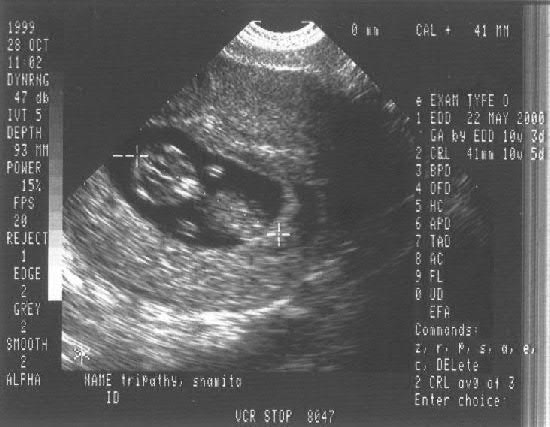

Week 10

Mom's comments:

This was my first ultrasound and the doctor pointed out his heartbeat on the monitor - just a tiny blinking thing! Kind of strange feeling.